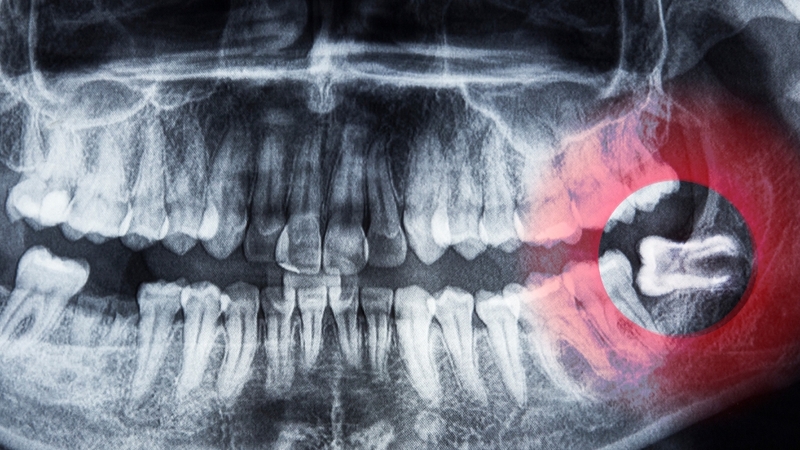

• Răng khôn mọc ngang hoặc mọc ngầm: Đây là tình trạng răng khôn nằm nghiêng hoặc nằm ngang trong xương hàm và không thể mọc lên theo hướng bình thường. Răng có thể tạo áp lực lên răng kế cận, gây đau hoặc làm tổn thương răng số 7.

Tình trạng răng khôn mọc lệch dễ chèn vào răng số 7 và tăng nguy cơ sâu răng

• Răng khôn mọc lệch hoặc mọc ngầm: Khi răng mọc sai hướng và chèn ép vào răng bên cạnh, nó có thể gây đau kéo dài, làm tổn thương răng số 7 hoặc gây tiêu xương quanh răng. Trong trường hợp này, bác sĩ thường chỉ định nhổ răng để tránh ảnh hưởng đến các răng lân cận.

• Hình thành u nang quanh răng khôn: Trong một số trường hợp, răng khôn mọc ngầm có thể dẫn đến sự hình thành u nang quanh chân răng. Nếu không được xử lý kịp thời, u nang có thể gây tổn thương xương hàm và các cấu trúc răng lân cận.